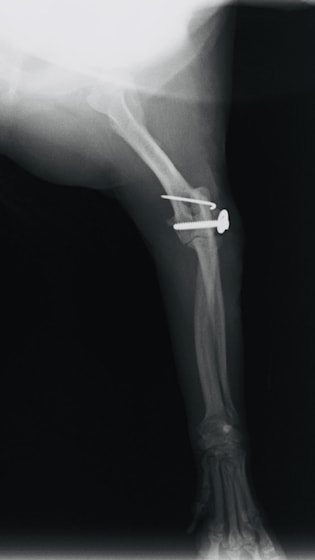

症例3:キルシュナーワイヤーのピンニングによる整復

ペルシャ猫 11ヶ月齢 雄

他院にて左大腿骨遠位の成長板骨折(salter-harrisⅠ型)が認められており、治療相談を目的として来院。当院にて、キルシュナーワイヤーを用いたピンニングにより骨折部位の整復を行いました。術後の経過は良好で、現在も経過観察中です。

術前レントゲン

術後レントゲン

機器

Arthrex社のターゲティングデバイスを用いてピンニングの位置を調整することで、確実な固定を行っています。当院ではこの手術器具以外にも、人の手術にも使用される様々な器具を導入し、手術精度を高め、また医療メーカーと新しい器具の開発、試作にも取り組んでおります。